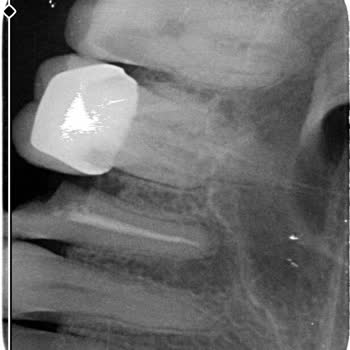

Ataşehir Ağız ve Diş Sağlığı Hastanesi'nde kanal tedavisi olmam gereken dişime 'derin dolgu ile kurtarırız' diyerek derin dolgu yapan Doktor *** nedeniyle sürekli dişimde apse oluşmaya başladı. Kontrole gidip şikayetimi söylediğimde Endodonti bölümüne, yani kanal tedavisi olmam gerektiği söylendi. B...